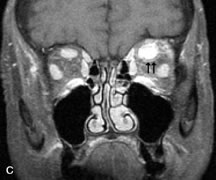

INTRAOCULAR TUMORS

On MRI, uveal melanomas have a typical appearance that helps to differentiate them from other primary and secondary intraocular tumors as well as choroidal detachments. Pigmented melanomas are hyperintense on Tl-weighted images, hypointense on T2-weighted studies, and hyperintense on proton density–weighted examinations (Fig. 24).30,31,50,80–82 These signal characteristics have been attributed to the paramagnetic properties of melanin because of stable free radicals that shorten the T1 and T2 relaxation times. Moderate enhancement is seen on postgadolinium T2-weighted images. Gadolinium-enhanced T1-weighted images are particularly sensitive in detecting choroidal melanomas.83 MRI may be less sensitive in detecting extrascleral extension of tumor than echography performed by an experienced ultrasonographer.84

Fig. 24. A. T1- and (B) T2-weighted MR scans demonstrate a small nodular intraocular mass (arrows) that is very hyperintense on the T1-weighted scan and hypointense on the T2-weighted image. This signal intensity pattern is due to the presence of free radicals within melanin granules. C and D. Postcontrast fat-suppressed T1-weighted scans demonstrate homogeneous intense enhancement of the lesion and no evidence of seleral penetration or optic nerve invasion.